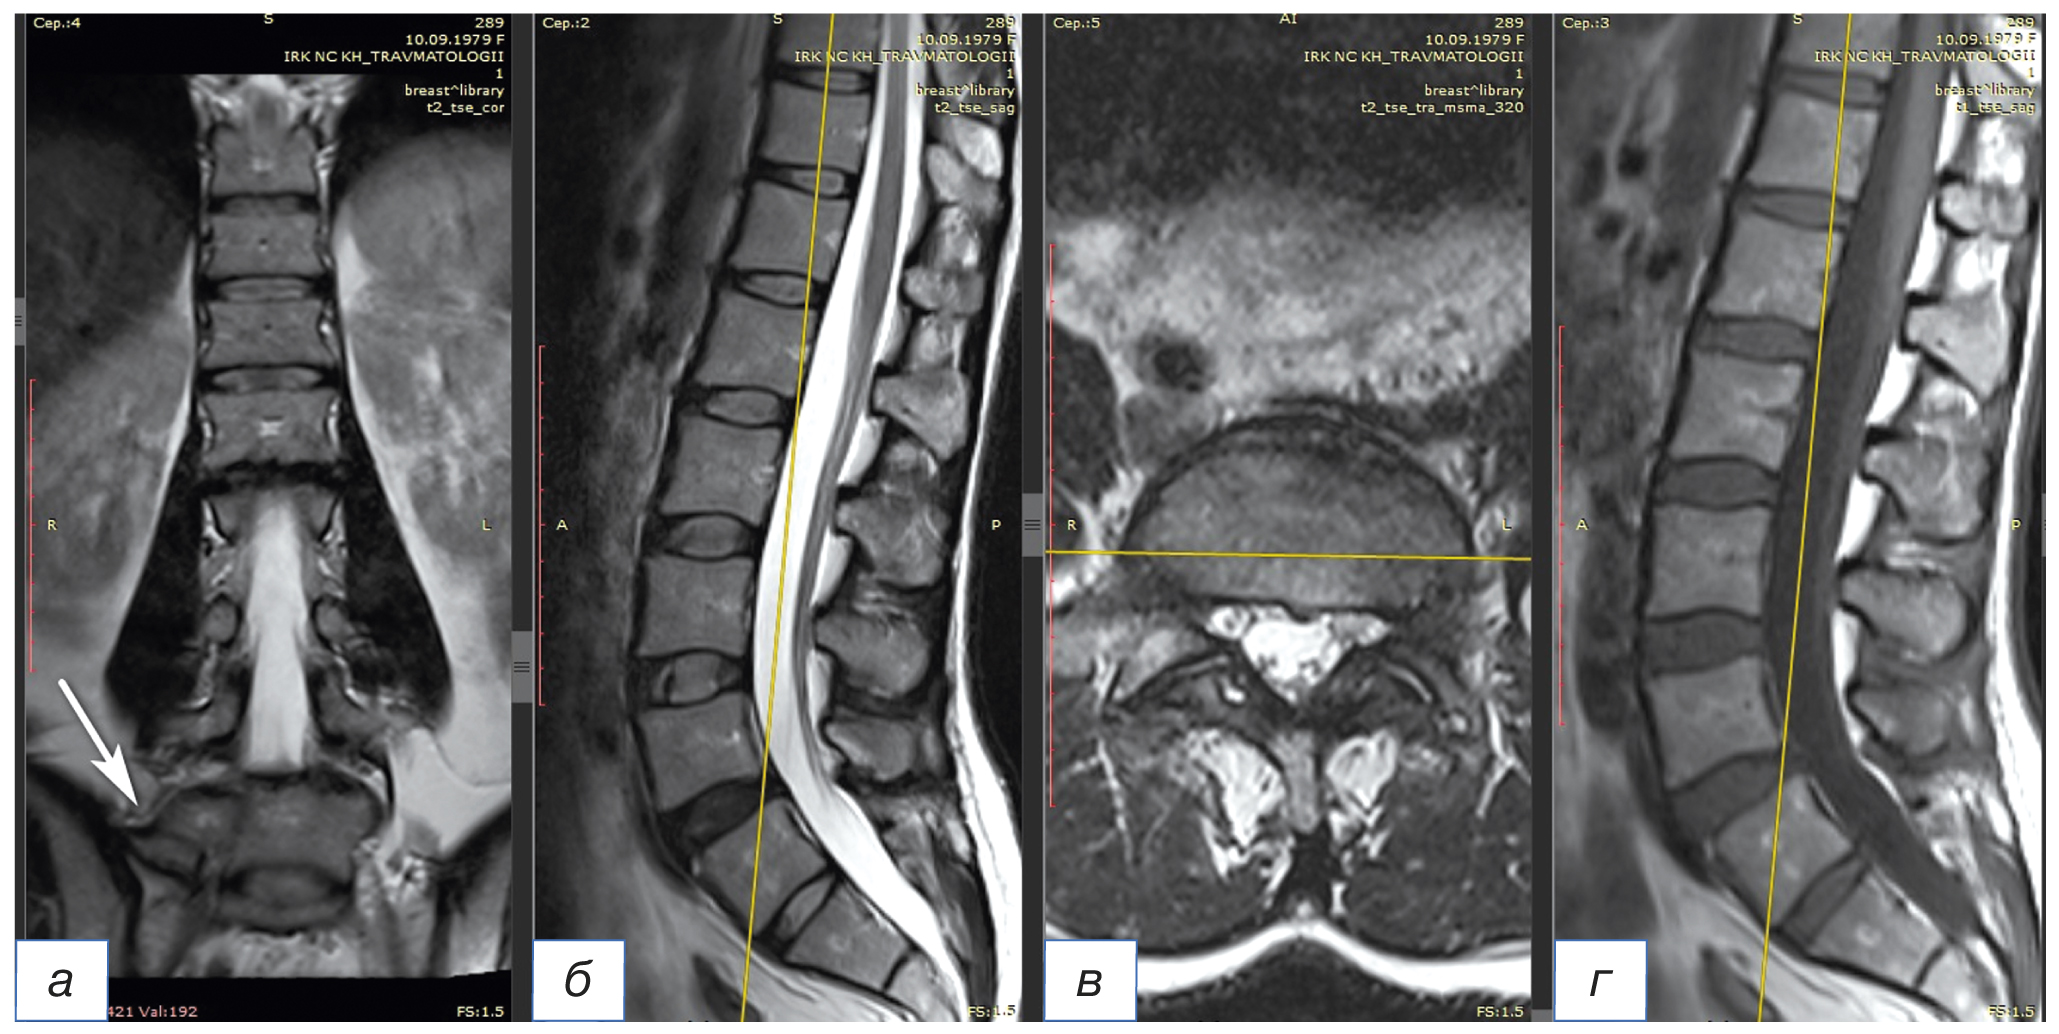

По данным магнитно-резонансной томографии (МРТ) поясничного отдела позвоночника сдавления спинномозговых корешков не выявлено (рис. 2).

Рис. 2. Магнитно-резонансная томография, Т2-взвешенное изображение, фронтальная (а), сагиттальная (б) и аксиальная (в) проекции; Т1-взвешенное изображение, сагиттальная проекция (г). Неоартроз между поперечным отростком и боковой массой крестца (белая стрелка). Сдавления спинномозговых корешков не определяется

Fig. 2. Magnetic resonance imaging Т2-weighted image, frontal projection (а), sagittal projection (б), and axial projection (в); Т1-weighted image, sagittal projection (г). Neoarthrosis between the transverse process and lateral mass of the sacrum (white arrow). Compression of the spinal roots is not determined